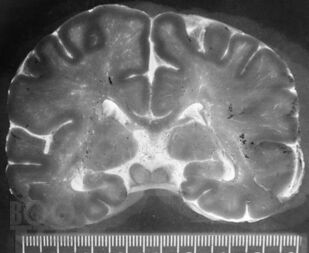

Это первая отечественная книга по патологии головного мозга у новорожденных и детей раннего возраста. Книга состоит из 7 глав, в которых рассмотрены вопросы развития головного мозга во внутриутробном периоде, этиология, патогенез, патоморфология и клинические проявления основных поражений мозга, а также внутричерепные кровоизлияния и пороки развития, в том числе уникальные. В книге также изложены новые и дискуссионные вопросы диагностики заболеваний, приведены классификации поражений, уточнены вопросы нозологии в детской неврологии, которые изучены недостаточно. Читатель получит сведения о том, насколько велико разнообразие форм поражений головного мозга у детей, как эти поражения отличаются от патологии мозга у взрослых и какова роль инфекций, гипоксии, родовой травмы и других факторов в их происхождении. Текст сопровождают более 450 цветных иллюстраций (фотографии, схемы и графики). Книга предназначена для патологов, педиатров, акушеров, перинатологов, инфекционистов, детских невропатологов, неонатологов, реаниматологов, специалистов нейровизуализационных методов исследования и судмедэкспертов. Книга может служить учебным пособием или справочником по основным заболеваниям головного мозга у новорожденных и детей раннего возраста.